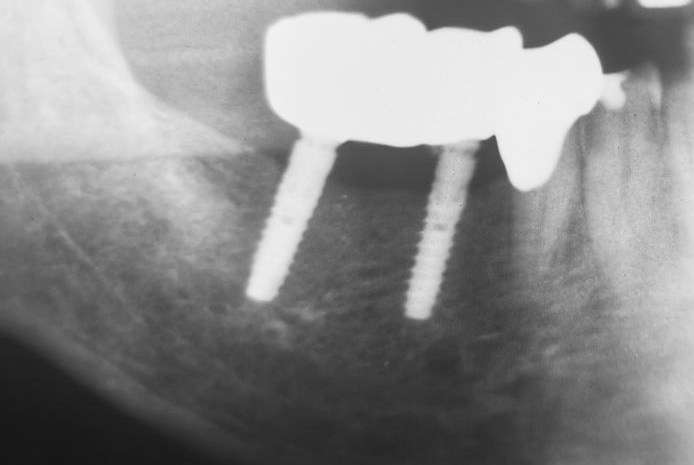

Insertion: at 45 a 12 mm long BioniQ Plus implant with Ø 2.9 mm and at 46 an equally long implant with Ø 3.5 mm. Both implants have a pronounced machined neck to prevent plaque accumulation over time.

The implants were inserted with primary stability and with the machined surface up to bone level. The X-ray check confirms that the BioniQ Plus implants inserted are of sufficient length.

The X-ray 14 months later shows a stable peri-implant bone level, which may have increased distally to the 2.9 implant.